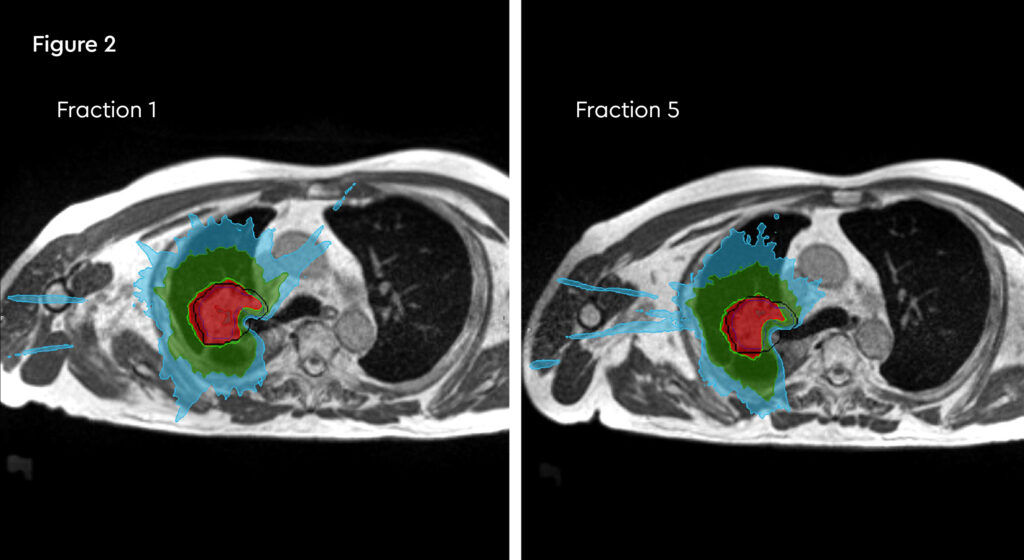

At each session, daily adaptation was performed to account for changes in the position of the prostate and for variable bladder and bowel filling. Figure 1 and figure 2 illustrate the typical differences seen between the original planning MRIdian scan and that seen on the day of treatment due to day-to-day organ movement. Figure 3 and figure 4 illustrate how these movements were accommodated with the on-table plan adaptation.

Figure 1 and figure 2 illustrate the typical interfraction movement as seen on the MRI scan. Figure 3 and figure 4 demonstrate the daily changes of the patient’s internal anatomy whilst figure 5 and figure 6 show the adaptive radiotherapy plan.

Fig 2: Daily re-contouring of a patient with central lung tumour. MRI scans from fraction 1 and fraction 5 show the extent of movement and variation and subsequent re-planning during adaptive treatment